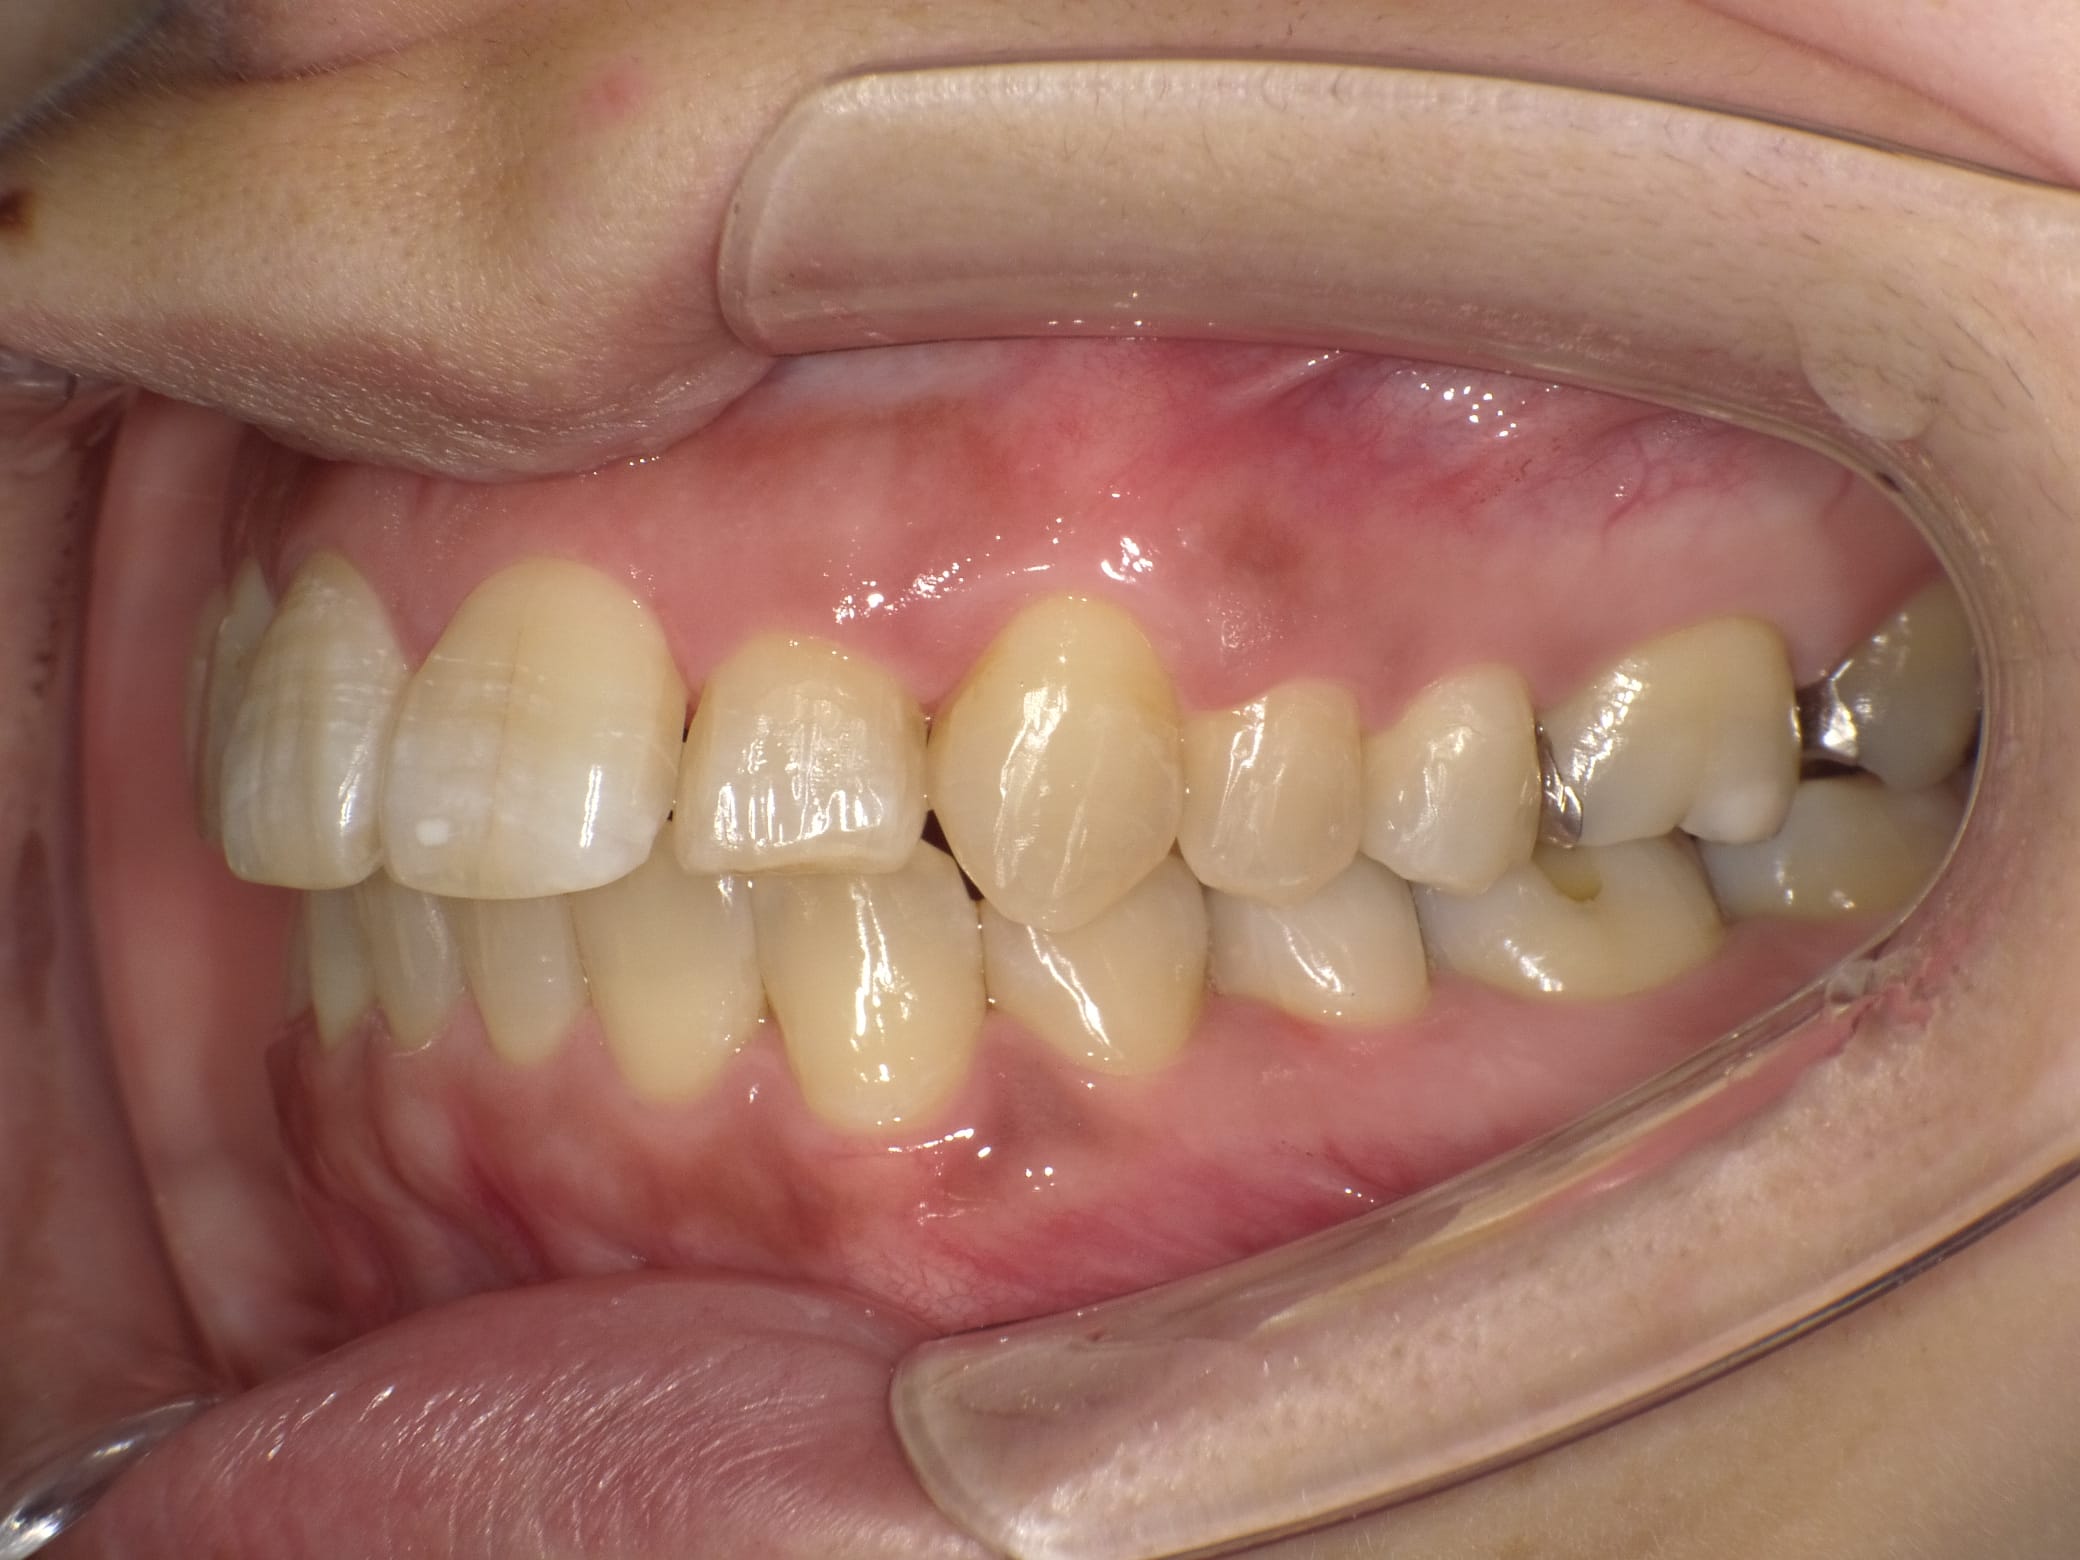

右の奥歯を過去に他院でインプラントをした方が、当院で左下や上の歯のインプラントをする為に転院してくださった患者様です。

インプラントは高額な治療ですが、どこの位置にどの角度で埋入するかが、とても大事というのがわかりやすかったので、患者様に投稿することをお願いして挙げさせていただきました。

インプラントを快適に長く使って頂くには、菌と力のコントロールが大事なのですが、前のものは位置が悪く、汚れも溜まりやすいし、咬む力も変な方向にかかってしまう仕上がりになっています。

被せ物のクオリティーもその歯科医院がどこの技工所にどのブランドで頼むかで全く変わってきます。

インプラントをご検討の方、すでに行った方は参考にしてください。